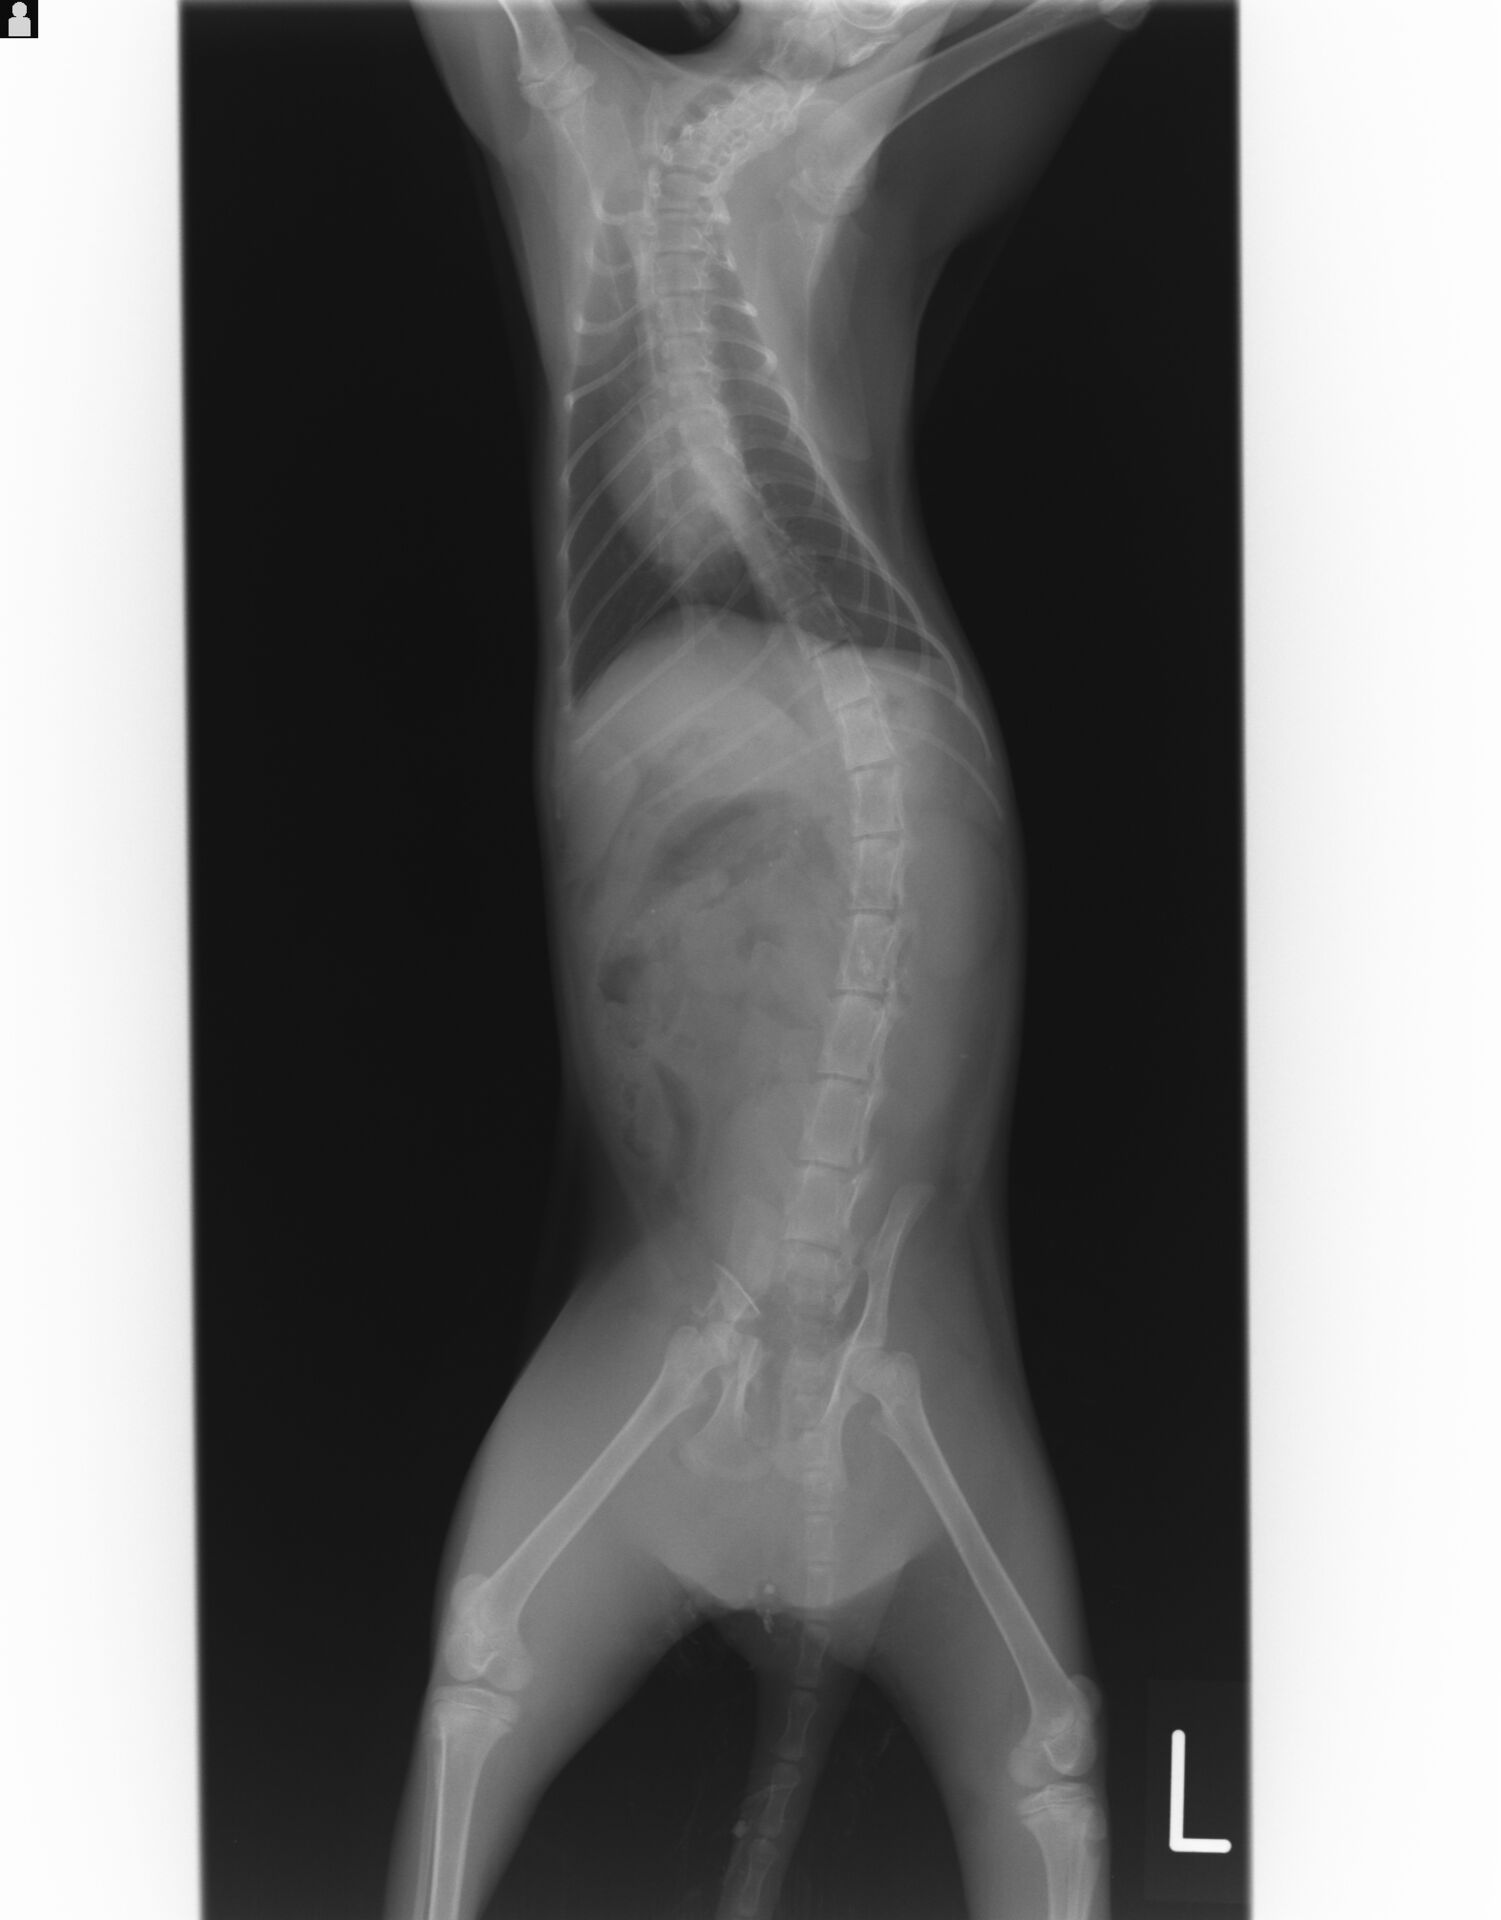

ある朝、前夜に夜間救急動物病院に連れて行ったという野良の子猫が連れて来られました。夜間救急で撮影したレントゲン写真を見ますと膀胱などの内臓や、手足の骨には異常はありませんでしたが、

骨盤が骨折し、股関節を脱臼していました。また股関節の辺りの皮膚が裂けており、夜間救急で縫合されていました。

当然、動くことができなくて、ショックと痛みのせいで食欲もないとのことでしたので、入院して点滴を始めました。骨盤の方は安静にしていれば、子猫ですので、家ネコとしてなら普通に生活できると判断し、手術しないことにしました。